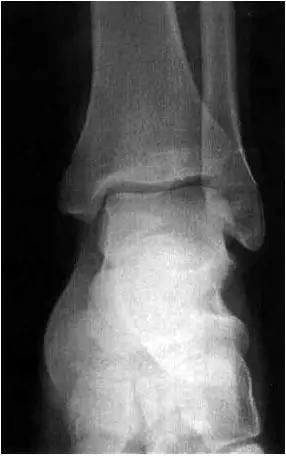

男,11岁,自述后踝下方疼痛,活动时为甚,并有一突起。

- 踝关节正侧位X 线平片,侧位片均显示距骨后方有三角形或椭圆形的距后三角骨。部分病例伴有轻度的踝关节骨性关节病。

- MRI 检查示距后三角骨及周围软组织有水肿信号,距后三角骨和距骨之间正常的低信号纤维连接中断,出现液性信号。